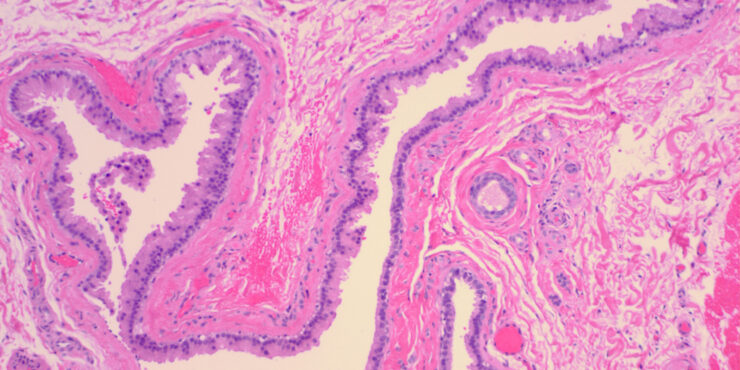

Read MoreApocrine hidrocystoma =الكيسوم العرقي المفترز Apocrine hidrocystoma The clinical appearance of a pea-sized cyst near the inner canthus of the eye, which contains a thin clear or pigmented fluid, suggests an apocrine hidrocystoma; however, histologic examination often is required to establish a specific and definitive diagnosis. Upon histologic examination, apocrine hidrocystomas show large unilocular or […]